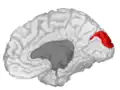

![]() Medial surface of left cerebral hemisphere. (Cuneus visible at left in red.) | |

The cuneus (from Latin 'wedge'; pl.: cunei) is a smaller lobe in the occipital lobe of the brain. The cuneus is bounded anteriorly by the parieto-occipital sulcus and inferiorly by the calcarine sulcus.

Medial surface of left cerebral hemisphere. Cuneus is visible at left in green. -